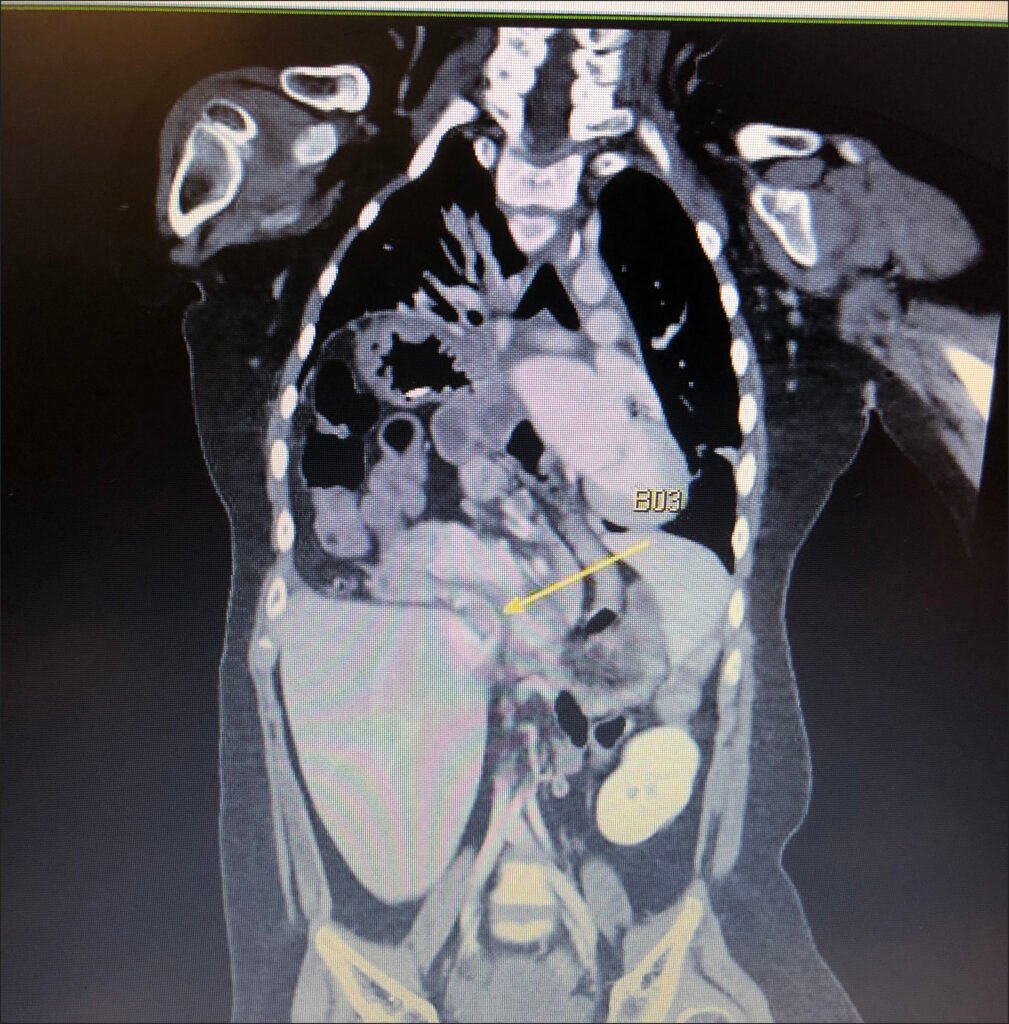

A rare type of hernia, approximately six inches in size was found in my son’s body, which had caused most of his abdominal organs to be pulled upward, exerting pressure on his lungs.

Surgery was presented as the only possible solution. However, due to the complexity and severity of the condition, the surgical team strongly advised against proceeding with the operation, warning us that there was a very high chance that my son would die on the operating table.